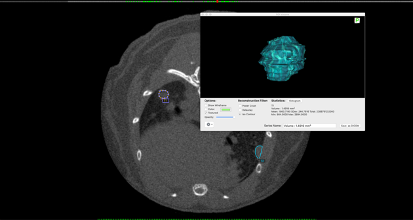

Figure C. Example of tumor volume analysis using OsiriX MD.

(Background) A lung tumor-bearing slice with two ROIs (=tumor) encircled in purple (T1) and in blue (T2). (Foreground) T1 tumor volume calculation and representation.